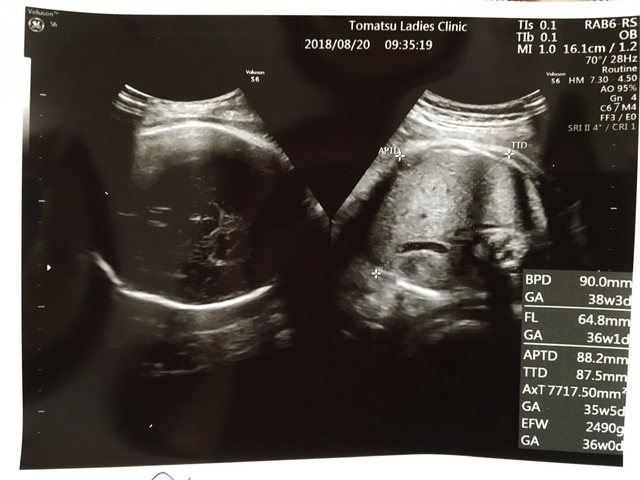

37週6日(37w6d・女の子)|あさママン(35歳)

エコー写真撮影時のエピソード:

しっかりご飯たべて、ゆっくりするのが1番なんだと 思いました。

貧血がひどいので 薬を出されてました。赤ちゃんが小さかったので10日間 入院しないといけなくなりました。38週2日ですが入院のおかげなのか3066まで大きくなっていました。産まれてくるときにはどんなけ大きくなってるのかちょっと不安です。